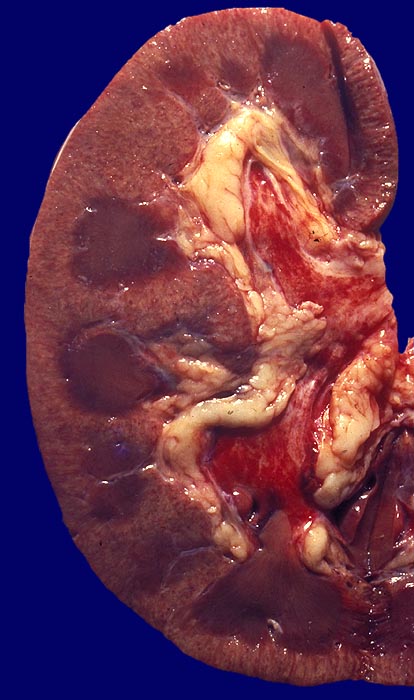

PathoPic ID 2191 - Akute Glomerulonephritis

Akute Glomerulonephritis

Entzündung / Reparatur

Niere

Nierenschnittfläche mit streifiger Hyperämie der Nierenrinde und Hämorrhagien in der Nierenbeckenschleimhaut.

Makroskopie